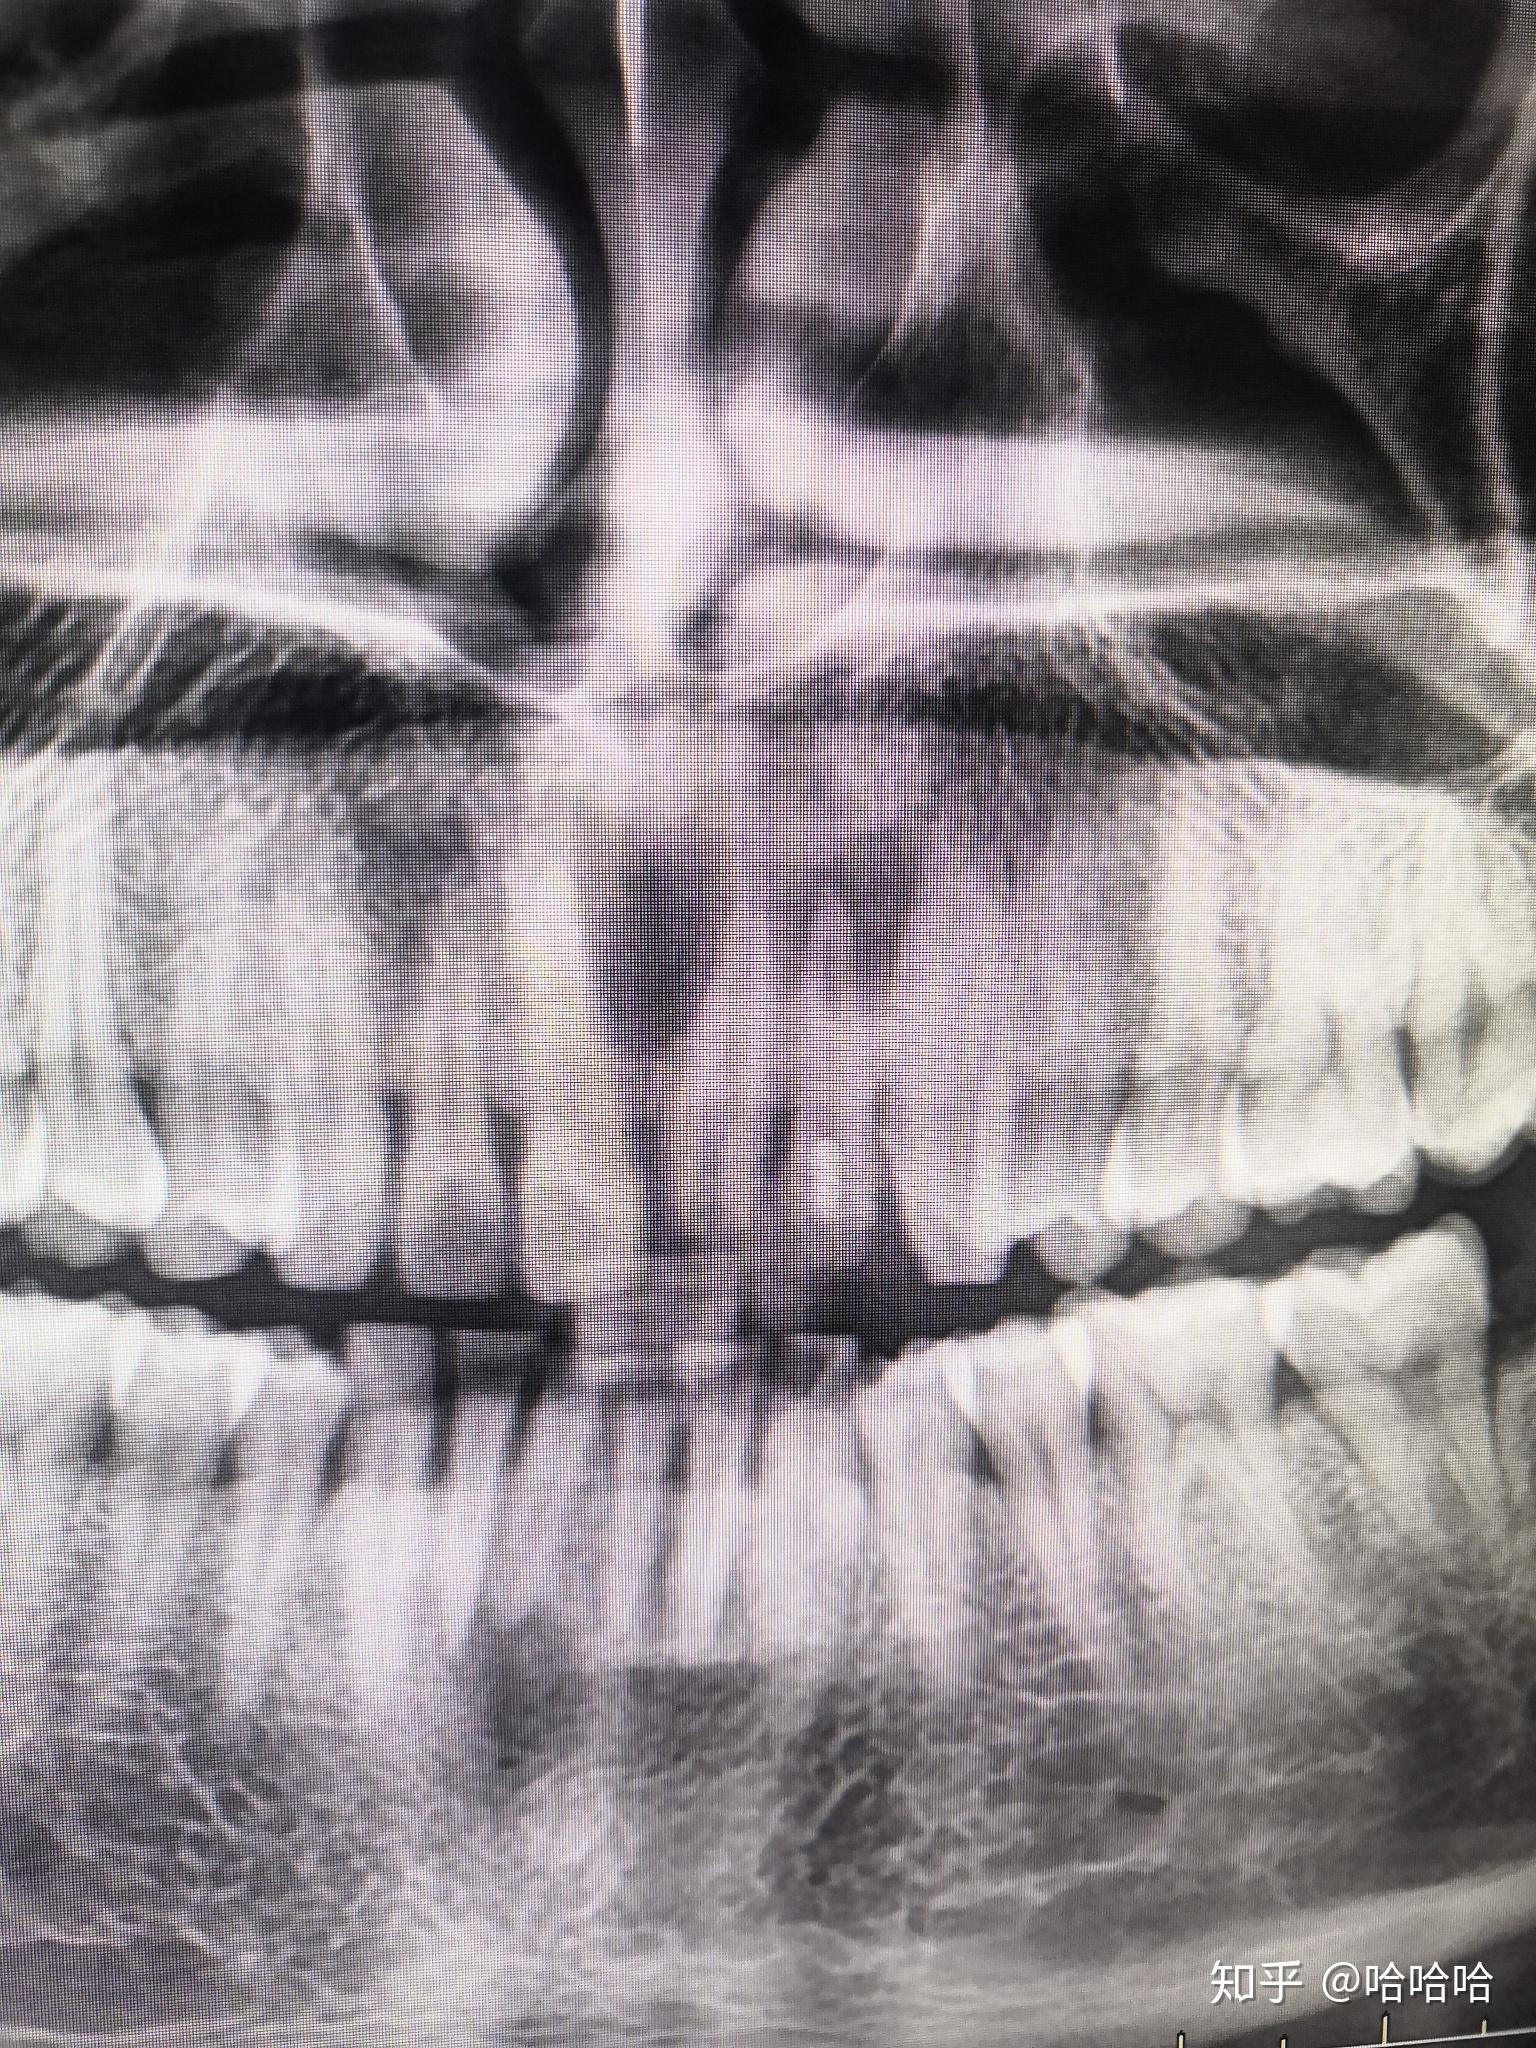

根尖囊肿x片

根尖囊肿